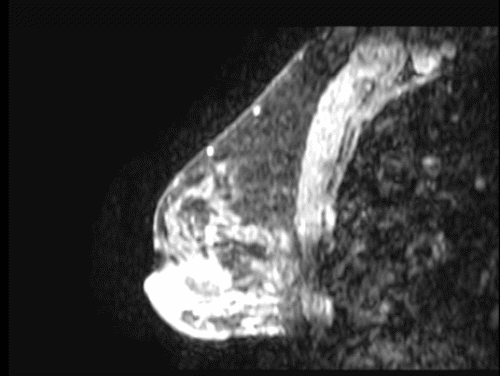

Over the next six months, the patient reported enlargement of the mass and slight tenderness. A right breast ultrasound was suggestive of a 1.5 cm fibroadenoma. One month later, a diagnostic mammogram demonstrated diffusely increased parenchymal density and skin thickening but no dominant mass. Repeat ultrasound demonstrated a 5 cm hyperechoic area with a 1.2 cm central area of hypoechogenicity, a series of nodules, and "intense surrounding blood flow" (Figure 1). Core needle biopsy revealed a vasoformative lesion, favoring a hemangioma. In the operative note of the subsequent excisional biopsy, "extremely large vessels circumferentially around the mass" were noted. After a pathologic review locally and at a tertiary academic medical center, the final diagnosis was a well-differentiated angiosarcoma of the breast, which measured 1.2 cm by gross examination. Although the surgical margins were not specifically addressed, completion mastectomy was recommended.

Figure 1. Targeted Ultrasound of Right Breast Taken before Biopsy. Published with Permission

A) Hyperechoic mass with nodules within breast parenchyma

B) Blood flow within and surrounding mass